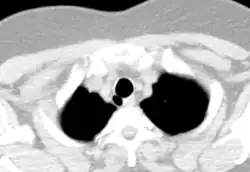

CT scan of the thorax (axial lung window)